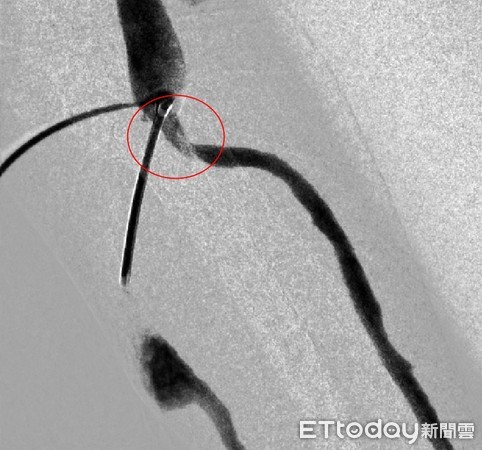

▲血管治療前後對比圖。(圖/亞大醫院提供)

劉殷佐指出,通常自體廔管若保養得當,通常可使用10年以上,但若沒有適當照護廔管,有時會發生血管狹窄的情形,嚴重者恐因狹窄引起血栓,出現生命危險,以林姓患者為例,因患者的廔管有出現滲血、阻塞等情形,必須在短時間內透過氣球擴張術等方式將血管撐開,以便血液流通,治療時間約15分鐘,結束後即可返家。